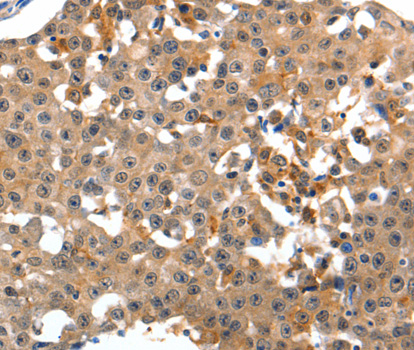

Immunohistochemistry of paraffin-embedded human breast cancer tissue using GRM1 antibody.